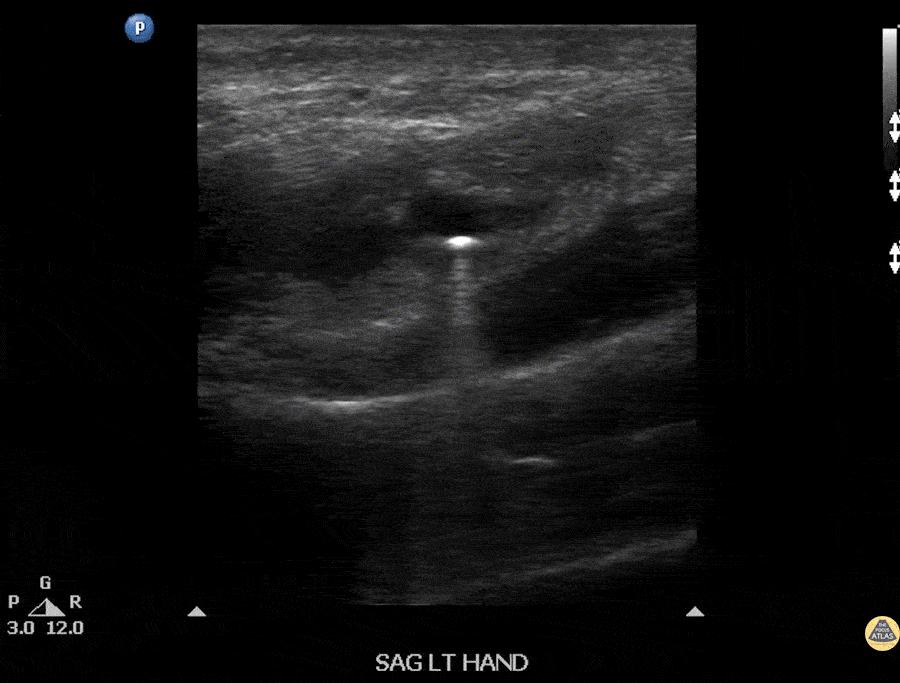

Soft Tissue - Foreign Body: BB within Hand

Ultrasound image of a BB lodged within a patient’s hand. Note the comet-tail artifact often seen deep to many solid structures. Image courtesy of Robert Jones DO, FACEP @RJonesSonoEM Director, Emergency Ultrasound; MetroHealth Medical Center; Professor, Case Western Reserve Medical School, Cleveland, OH View his original post here